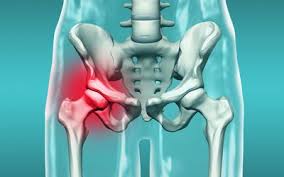

A hip fracture is a break in the upper part of the thigh bone femur which is the bone that fits into the socket of the hip joint. Gentle progressive strengthening exercises to. Treatment of hip stress fracture.

What would a physiotherapy treatment for a Hip Stress Fracture involve. Most people will need surgery to fix the fracture or replace all or part of their hip ideally on the same day theyre admitted to hospital or the day after. Treatment of hip stress fracture Immediately after a stress fracture is diagnosed the patient should discontinue all sports activities and walk with two crutches to apply less forces to the injured leg.

Medications for Stress Fractures You can take over-the-counter medications to manage pain. Initial treatment of a hip stress fracture may include X-rays a magnetic resonance imaging MRI scan or a bone scan to further evaluate your condition.